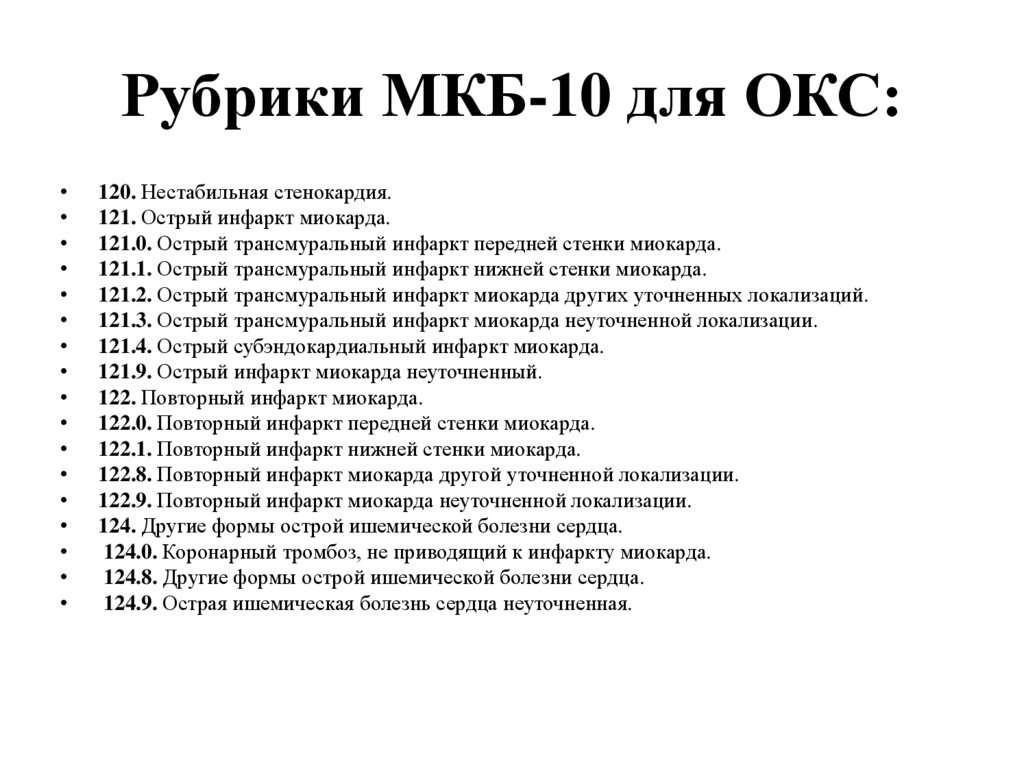

Код мкб 10 атерома головы

Код мкб 10 атерома головы 109 фото